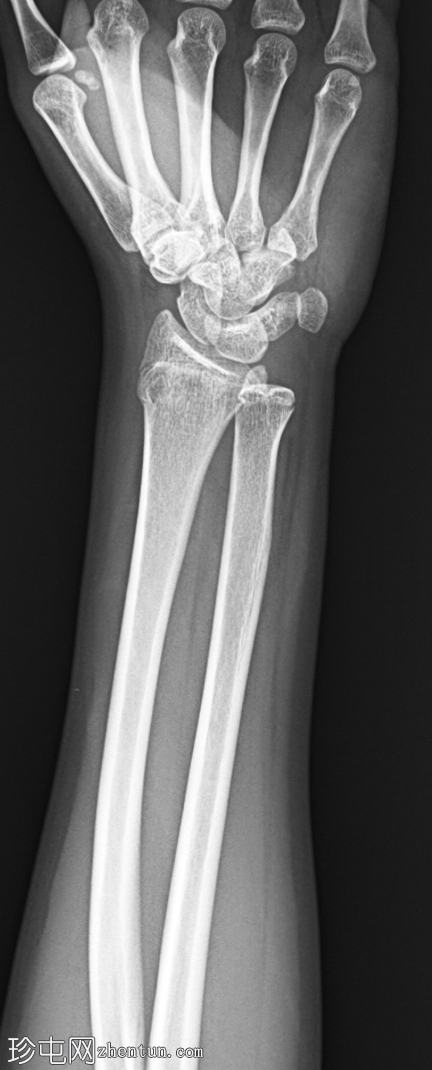

2.png

侧位片

左腕正位X线片显示桡骨远端干骺端背外侧皮质轻微弯曲,无皮质破裂或移位。无明显成角畸形或尺骨骨折。关节间隙和腕骨排列正常。

最终诊断:桡骨远端干骺端轻微嵌插(弯曲型)骨折。